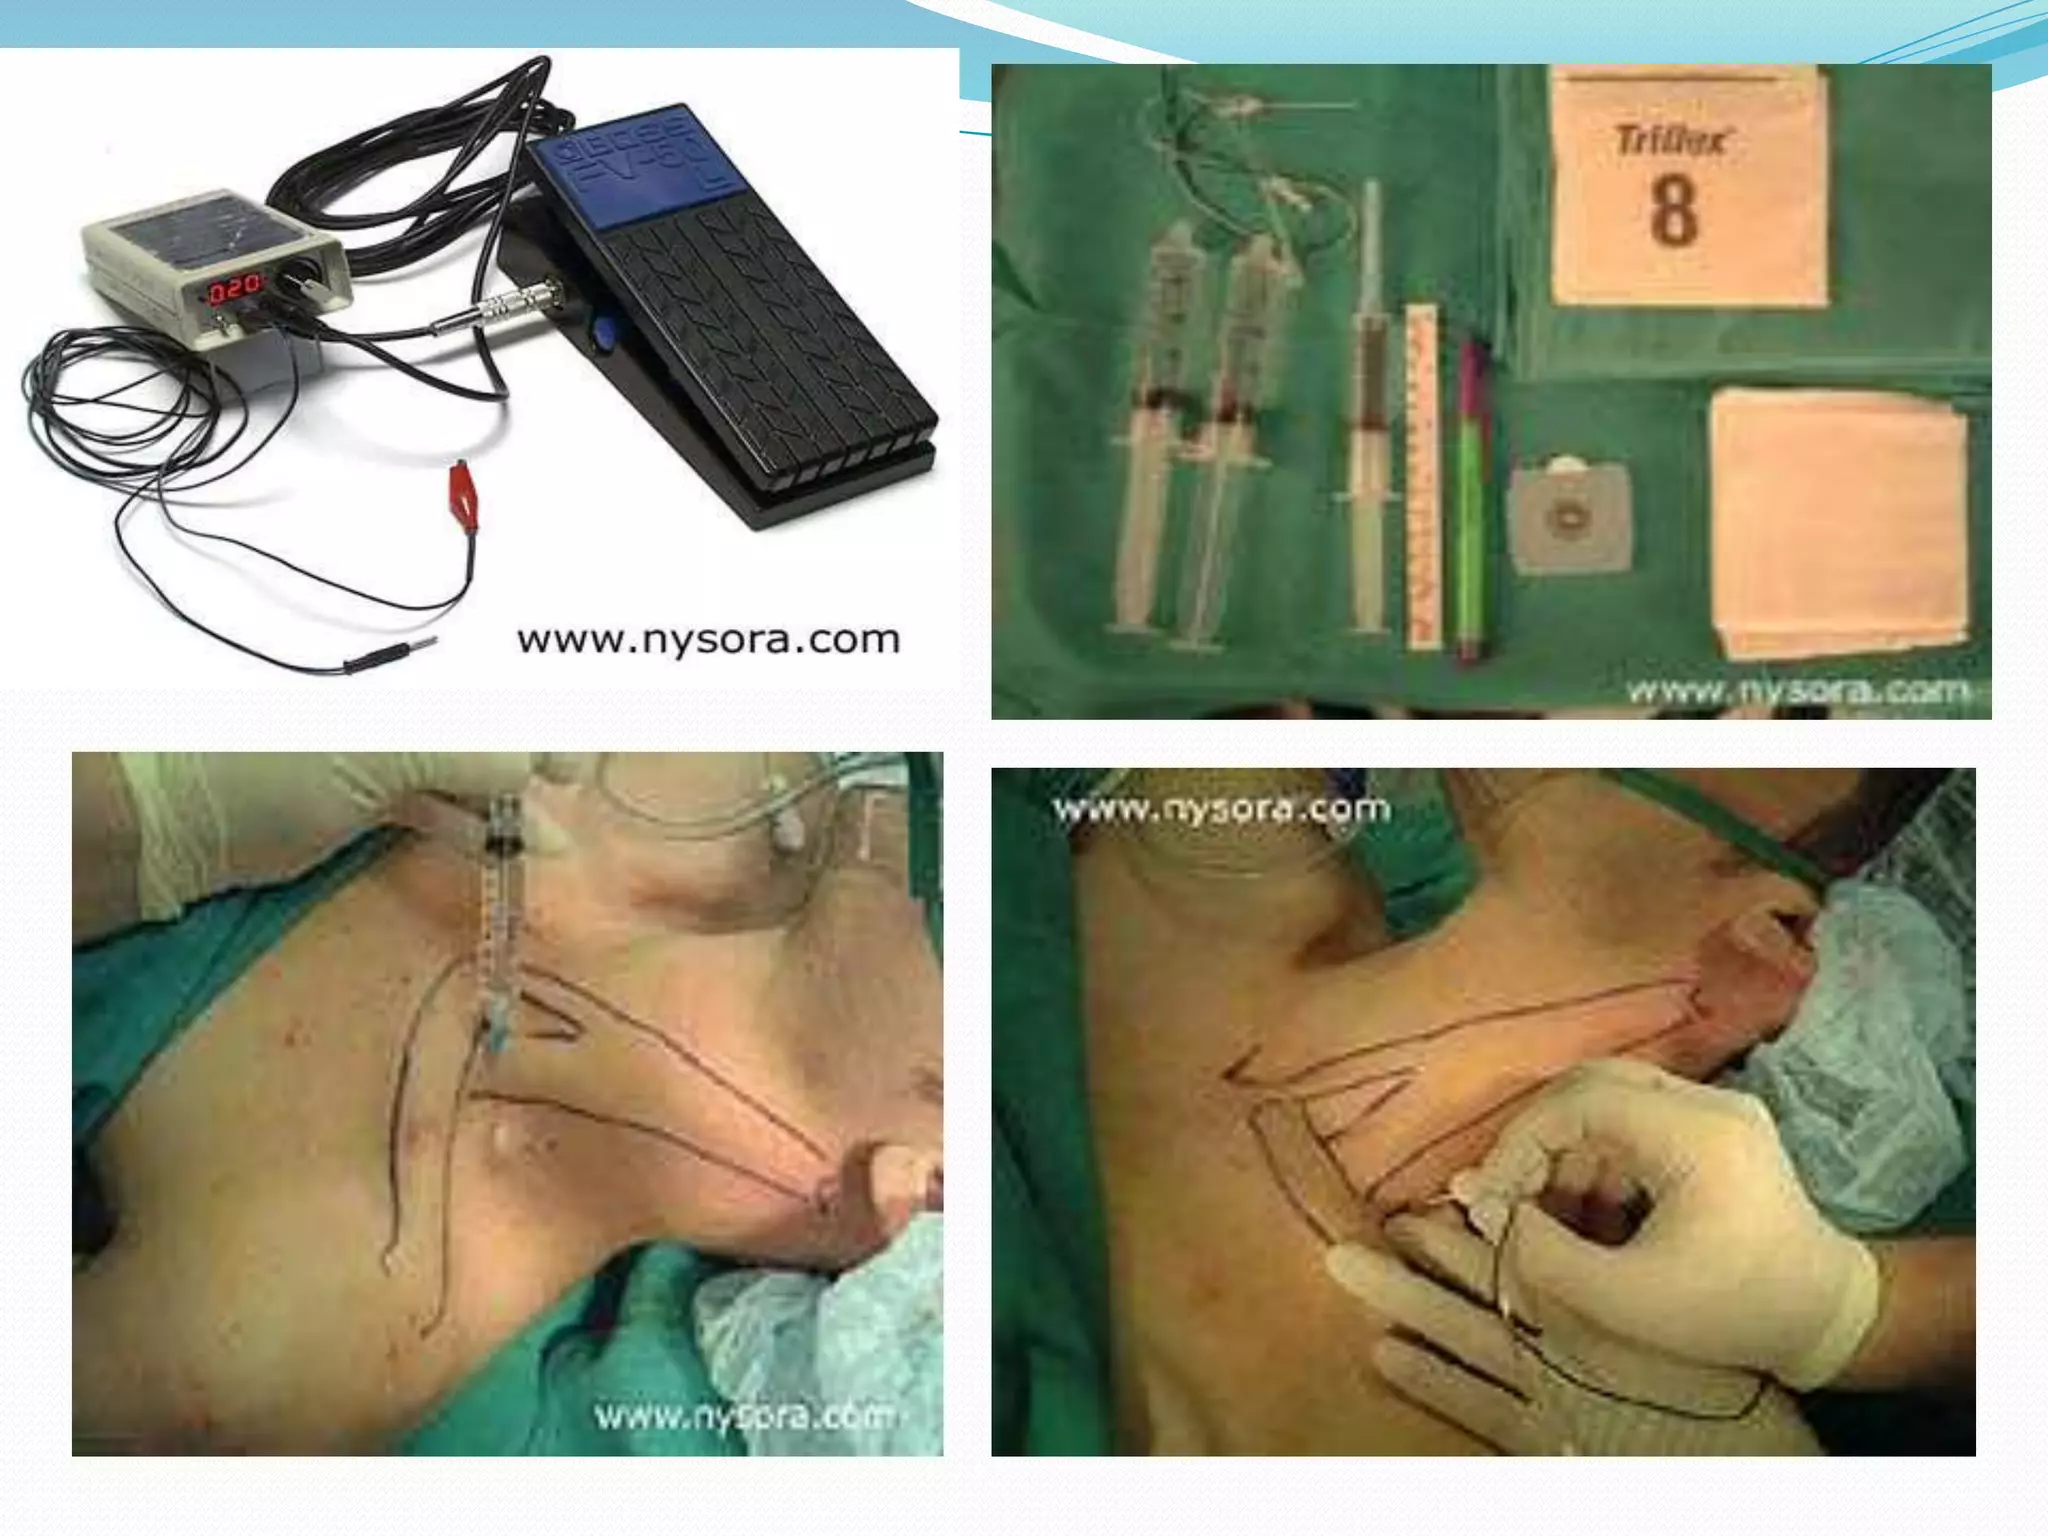

This document provides an overview of brachial plexus anatomy and techniques for brachial plexus nerve blocks. It begins with a description of the brachial plexus formation from cervical and thoracic nerve roots and its branching pattern. Four main approaches for brachial plexus nerve blocks are described: interscalene, supraclavicular, infraclavicular, and axillary. Details are provided on the anatomy and techniques for performing interscalene and supraclavicular brachial plexus blocks. Ultrasound guidance is discussed as an advancement which allows real-time visualization of needle and nerve. Complications are also summarized.